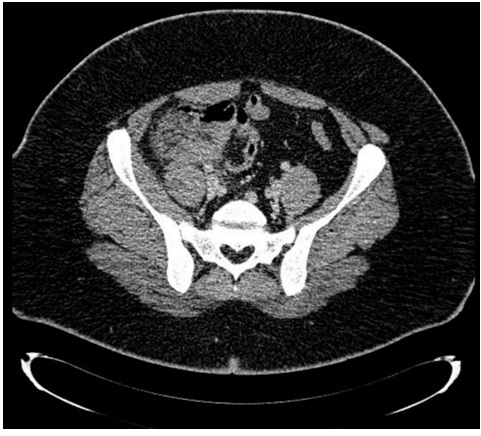

Con planteo de MIA el paciente ingresó para tratamiento antibiótico presentando una buena evolución. Se otorgó el alta a los 5 días, asintomático, indicando completar 5 días de antibióticos. Se controló en policlínica a la semana y al mes. A los 9 meses el paciente re consulta en emergencia por dolor en FID. Una nueva TC evidencia la presencia de un proceso inflamatorio ceco apendicular (Figura 2), reingresando para tratamiento antibiótico. La recurrencia sintomática motivó completar la valoración con videocolonoscopía (VCC) con ileoscopía y solicitud de marcadores tumorales a fin de descartar diagnósticos diferenciales, no presentando alteraciones. Dada buena evolución clínica - humoral, se otorgó el alta hospitalaria a los 7 días. A los 4 meses se solicitó control con TC, evidenciando la persistencia de una imagen patológica. El episodio de recurrencia y la persistencia de una imagen patológica tomográfica motivaron la AE. Fue realizada a los 10 meses, de coordinación por abordaje laparoscópico. El apéndice cecal se encontraba en situación latero cecal interno, involucrado en un proceso adherencial laxo (Figura 2). Se realizó la apendicetomía sin incidentes, otorgándose el alta a las 24 horas (Figura 2). Se otorgó el alta definitiva con el resultado de la anatomía patológica que evidenció infiltrado inflamatorio leucopiocitario difuso y transmural, en ausencia de elementos de malignidad.

Figura 2: Fuente: A: TC corte axial que evidencia al re ingreso proceso inflamatorio a nivel del FID, no se identifica apéndice cecal. B: TC de control a los 4 meses. Se evidencia la persistencia de imagen patológica (flecha roja). C: Intraoperatorio, apéndice cecal (en verde) D: Pieza abierta por borde anti mesentérico. Mucosa macroscópicamente sana elaboración propia.